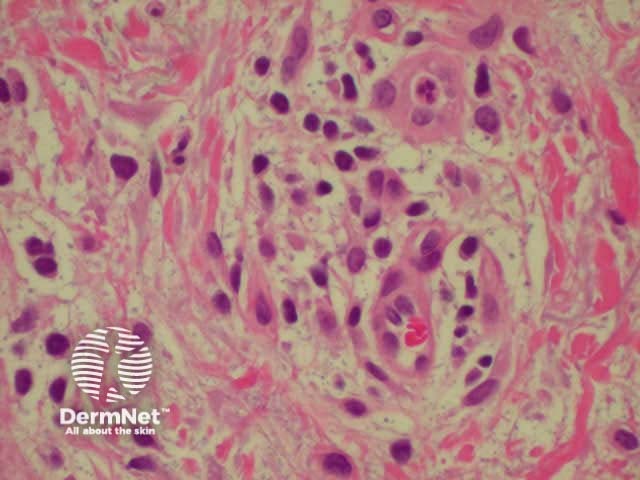

Histologically, dermatitis is characterised by inflammation of the epidermis and epidermis i.e perivascular lymphohistocytic infiltrate. The hallmark of acute dermatitis is spongiosis (intraepidermal vesicles). As eczema becomes more chronic, there is tendency for it to become more acanthotic (thickened epidermis) and less spongiotic.

Dermal inflammatory infiltrate